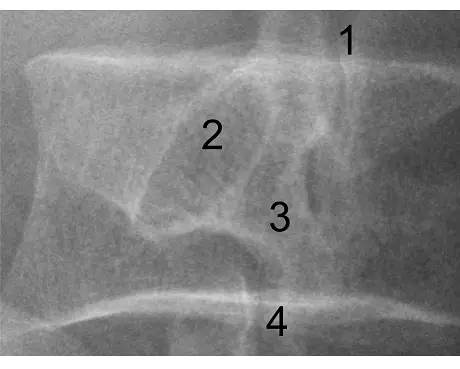

題目提供的影像是腰椎的斜位 X 光攝影(Oblique projection)。在腰椎斜位影像中,正常的解剖構造會呈現經典的「蘇格蘭狗(Scottie dog)」型態。我們可以依據此特徵來對應圖片上的數字標記:

- 標記 1:為蘇格蘭狗的「耳朵(Ear)」,解剖上對應上關節突(Superior articular process)。

- 標記 2:為蘇格蘭狗的「眼睛(Eye)」,解剖上對應椎弓根(Pedicle)。

- 標記 3:為蘇格蘭狗的「脖子(Neck)」,解剖上對應椎弓峽部(Pars interarticularis)。若此處發生斷裂,即為脊椎椎弓解離症(Spondylolysis),影像上會呈現「狗脖子戴項圈」的表徵。

- 標記 4:為蘇格蘭狗的「前腳(Front leg)」,解剖上對應下關節突(Inferior articular process)。